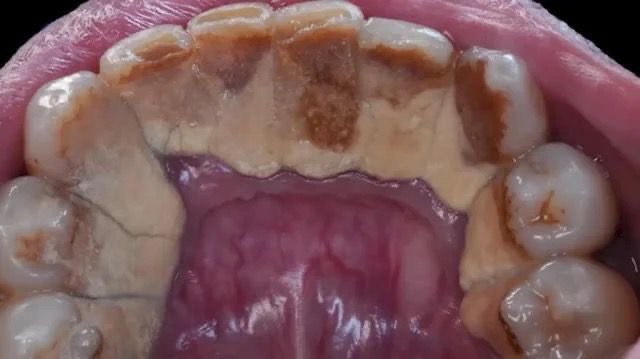

مضاعفات جير الأسنان🚨🚨

لا تقتصر أضرار جير الأسنان على التأثير على المظهر الجمالي للفم، ولكن تمتد لتشمل مضاعفات تصيب الأسنان واللثة وربما الصحة العامة

ومنها:

تسوس الأسنان🚨

يساهم تراكم الجير على الأسنان في تسوسها نتيجة صعوبة القدرة على تفريش الأسنان جيدًا واستعمال الخيط بسهولة.

أمراض اللثة🚨

يؤدي الجير إلى الإصابة بأمراض اللثة، ويعرف مرض اللثة في مراحله المبكرة بالتهاب اللثة وتشمل أعراضه ما يلي

احمرار اللثة وتورمها.🚨

نزف اللثة عند تفريش الأسنان أو استعمال الخيط.

يمكن علاج مرض اللثة في هذه المرحلة بالتفريش الجيد للأسنان واستعمال الخيط وغسول الفم، وعمل تنظيف عميق عند الطبيب.